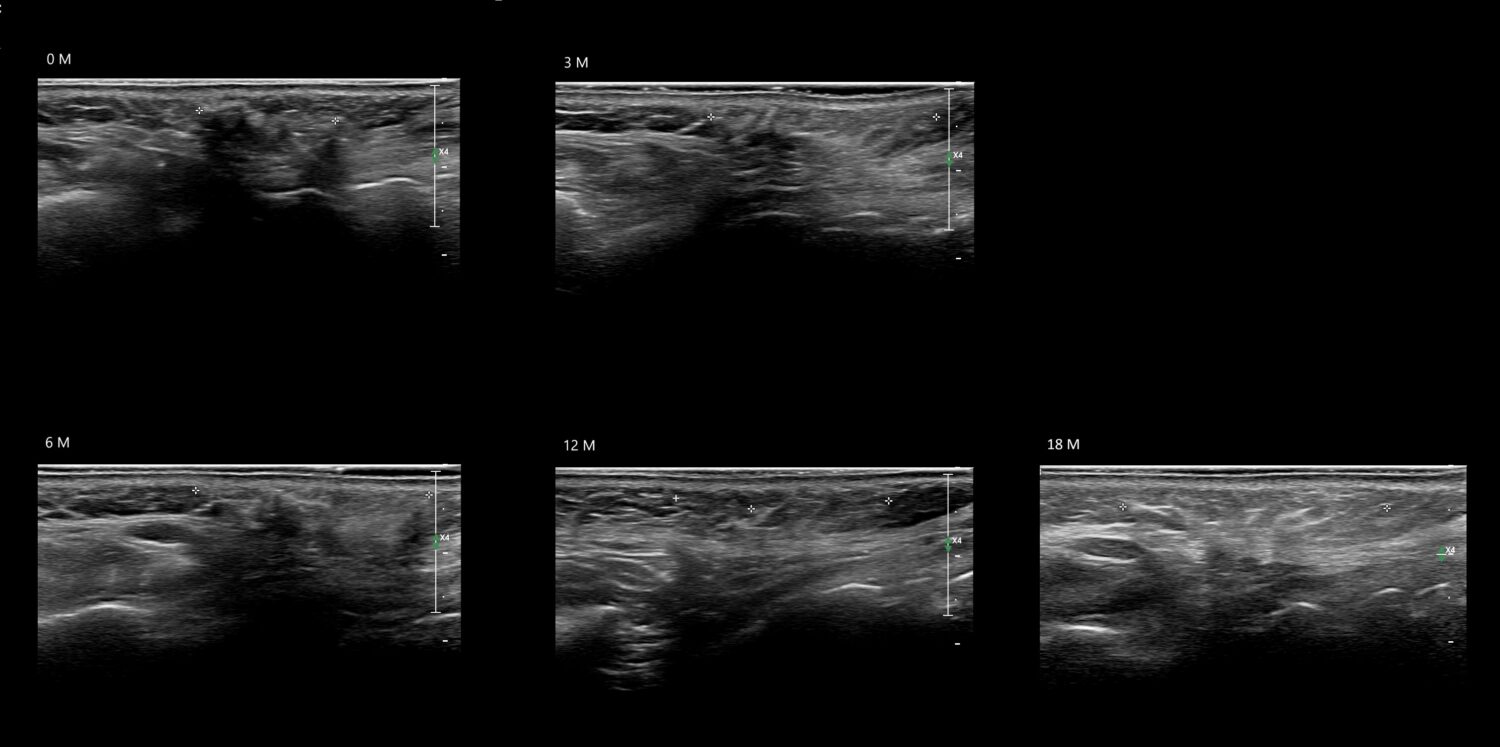

Draw in the image on the right where the fillers are located. To check if your answer is correct, please click on the secondary image.

Draw in the second image below where the fillers are located. To check if your answer is correct, swipe the first image to the right.